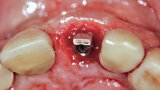

Fig. 24a: Depth control and rotational positioning were accurately

confirmed with the notch indicator on the template corresponding with the insertion tool (a). The occlusal view illustrated that the anti-rotational internal

conical–hexagonal connection was positioned towards the facial aspect (b).

Fig. 24b: Depth control and rotational positioning were accurately